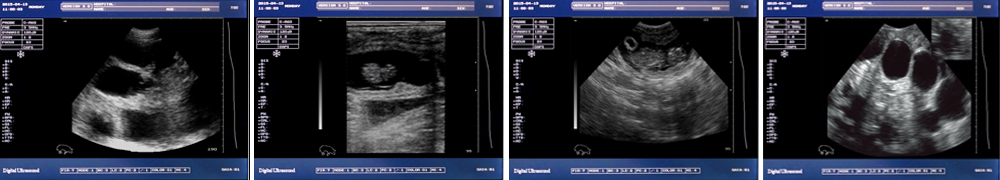

高清分辨率彩色液晶顯示屏,圖像更清晰

● 中小動物的肝、膽,脾、腎、膀胱、子宮、妊娠等各組織器官的檢查和病變的診斷;

● 卵巢等生殖系統(tǒng)疾病診斷;

● 妊娠、胎兒發(fā)育、胎兒活力和性別鑒定的診斷;